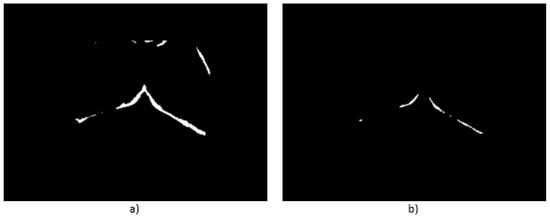

- Case 3, angiogenesis:The acquired histogram is shown in Figure 18a, and as in the previous cases, the pre-processing necessary to segment the breast regions can be followed step by step in Figure 18b–d. The segmented right and left breast are shown in Figure 18e,f, respectively. As in the previous case, a noticeable difference of temperatures can be seen in the thermogram in Figure 18a, with a lighter zone in the upper region of the left breast of the patient. This comparison is easier to achieve looking at Figure 18e,f.In Table 6 can be seen the estimation of the average difference of temperatures, which result in being 1.81 °C, with the left breast resulting in being hotter than the right breast, as expected. This is a clear indication of a detected problem, and now, the search for the hottest regions in the left breast is required. For this case, the difference of the maximum value and the standard deviation between the left and right sides is quite significant. In Figure 18, it is clear that one breast is lighter (or hotter) than the other.Watershed segmentation result can be seen in Figure 19. This time the hottest region is surrounding a cold zone and the resulting segmented shape can be associated with the one that blood vessels present resulting in an angiogenesis case. As mentioned earlier angiogenesis can be seen in early stages of breast cancer and subsequent medical exams are required, having the point of interest spotted in order to help the experts to correctly treat the patient.